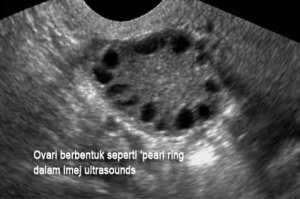

PCOS atau polycystic ovarian syndrome ialah keadaan yang boleh menganggu sistem peranakkan wanita dimana folikel-folikel yang terdapat didalam ovari tidak menjadi matang dan seterusnya gagal untuk mengeluarkan telur. Folikel-folikel terkumpul didalam ovari dan menjadi cysta-cysta kecil yang boleh dilihat melalui ultrasounds scan. Ia berlaku 6-10% dikalangan wanita dan di antara penyebab utama mengapa wanita gagal hamil.

- Ultrasound Pelvis- rahim dan ovari